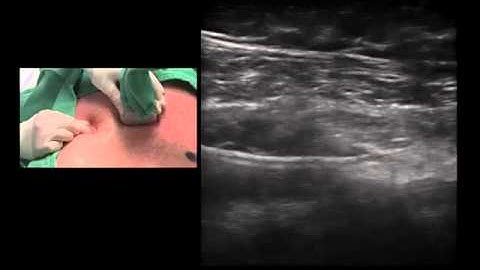

TAP BLOCK